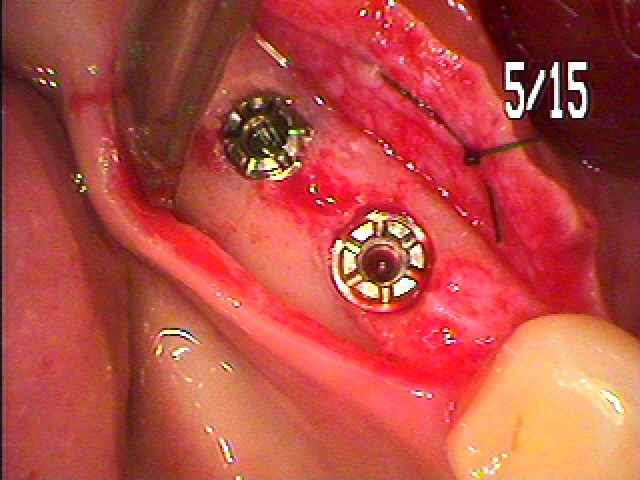

このように骨内にインプラントを埋入しています

4mmの13mmというインプラントを埋入しています